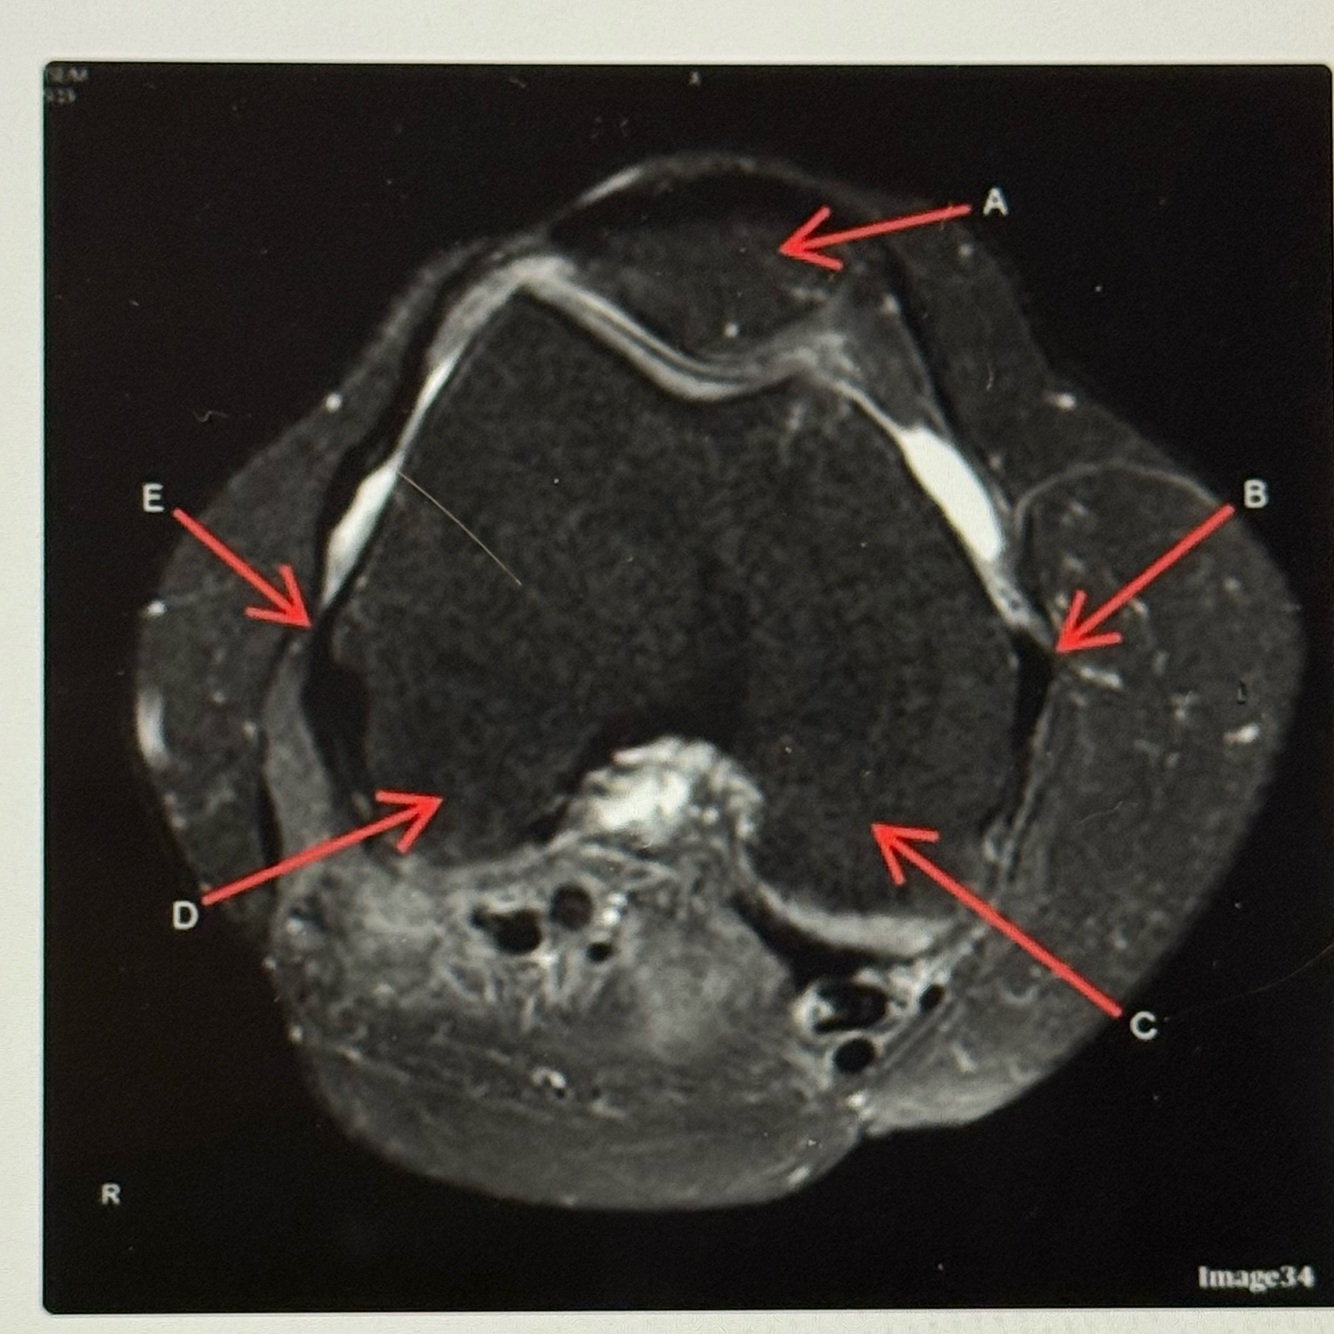

20

Q

Letter D points to the

A

Lateral femoral condyle

21

Letter C points to the

Medial femoral condyle

22

Letter B points to the

Medial

Collateral ligament (MCL)

23

Letter A points to the

Letter E points to the

Lateral collateral ligament (LCL)